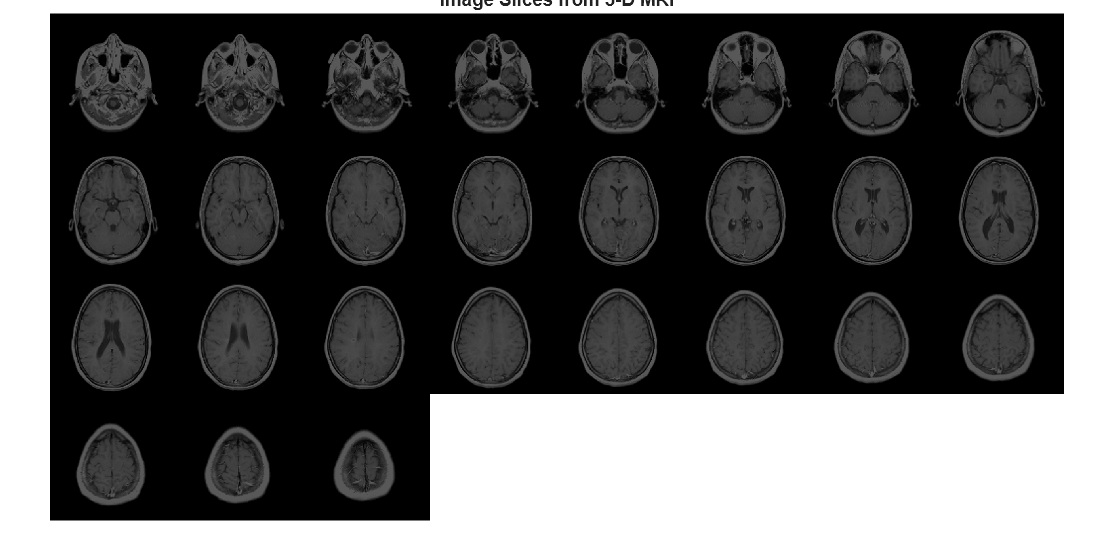

Examples